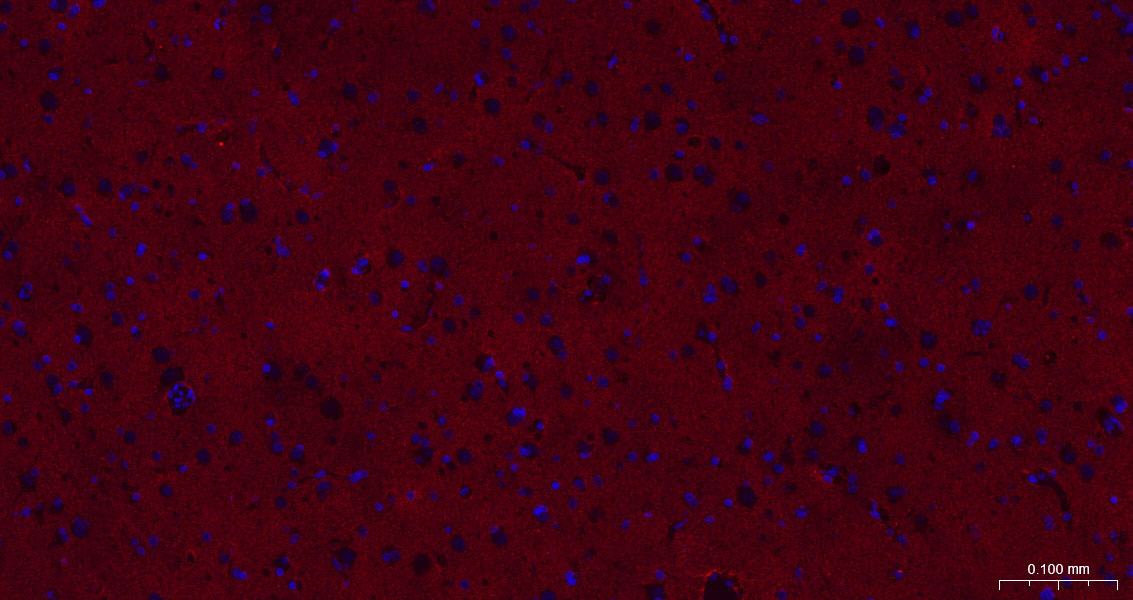

Paraformaldehyde-fixed, paraffin embedded Human Glioma; Antigen retrieval by boiling in sodium citrate buffer (pH6.0) for 15 min; The section was incubated with EAAT1 Monoclonal Antibody, Unconjugated (bsm-60880R) at 1:200 overnight at 4°C. Followed by conjugated Goat Anti-Rabbit IgG antibody (Red, bs-0295G-BF594), DAPI (blue, C02-04002) was used to stain the cell nuclei.